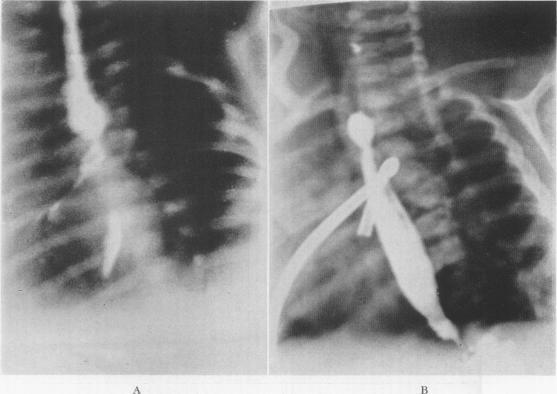

Congenital atresia of the esophagus with tracheo-esophageal fistula; treatment of surgical complications.

Ann Surg. 1955 Aug;142(2):204-13. doi: 10.1097/00000658-195508000-00006.